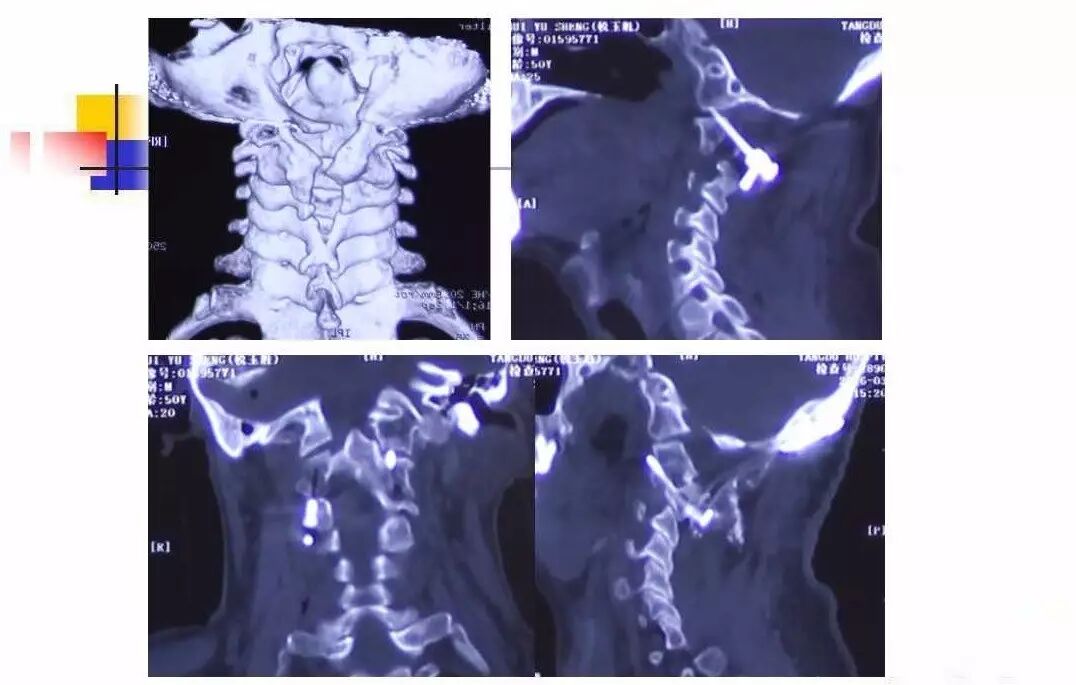

在脊柱神经外科、显微神经外科和颅底肿瘤外科前沿研究和临床诊治领域有着扎实的基础,为全国首批获得脊柱神经外科医师培训认证的神经外科医生。擅长颈椎病、椎管肿瘤及各种脊柱疑难疾病的诊治、脑肿瘤微创手术,尤其擅长颈椎退行性疾病的手术,率先在国内开展了颅底凹陷后路复位、颈前路减压融合等高难度手术,多年来收治了来自全国各地的大量患者,疗效达到国内领先水平。